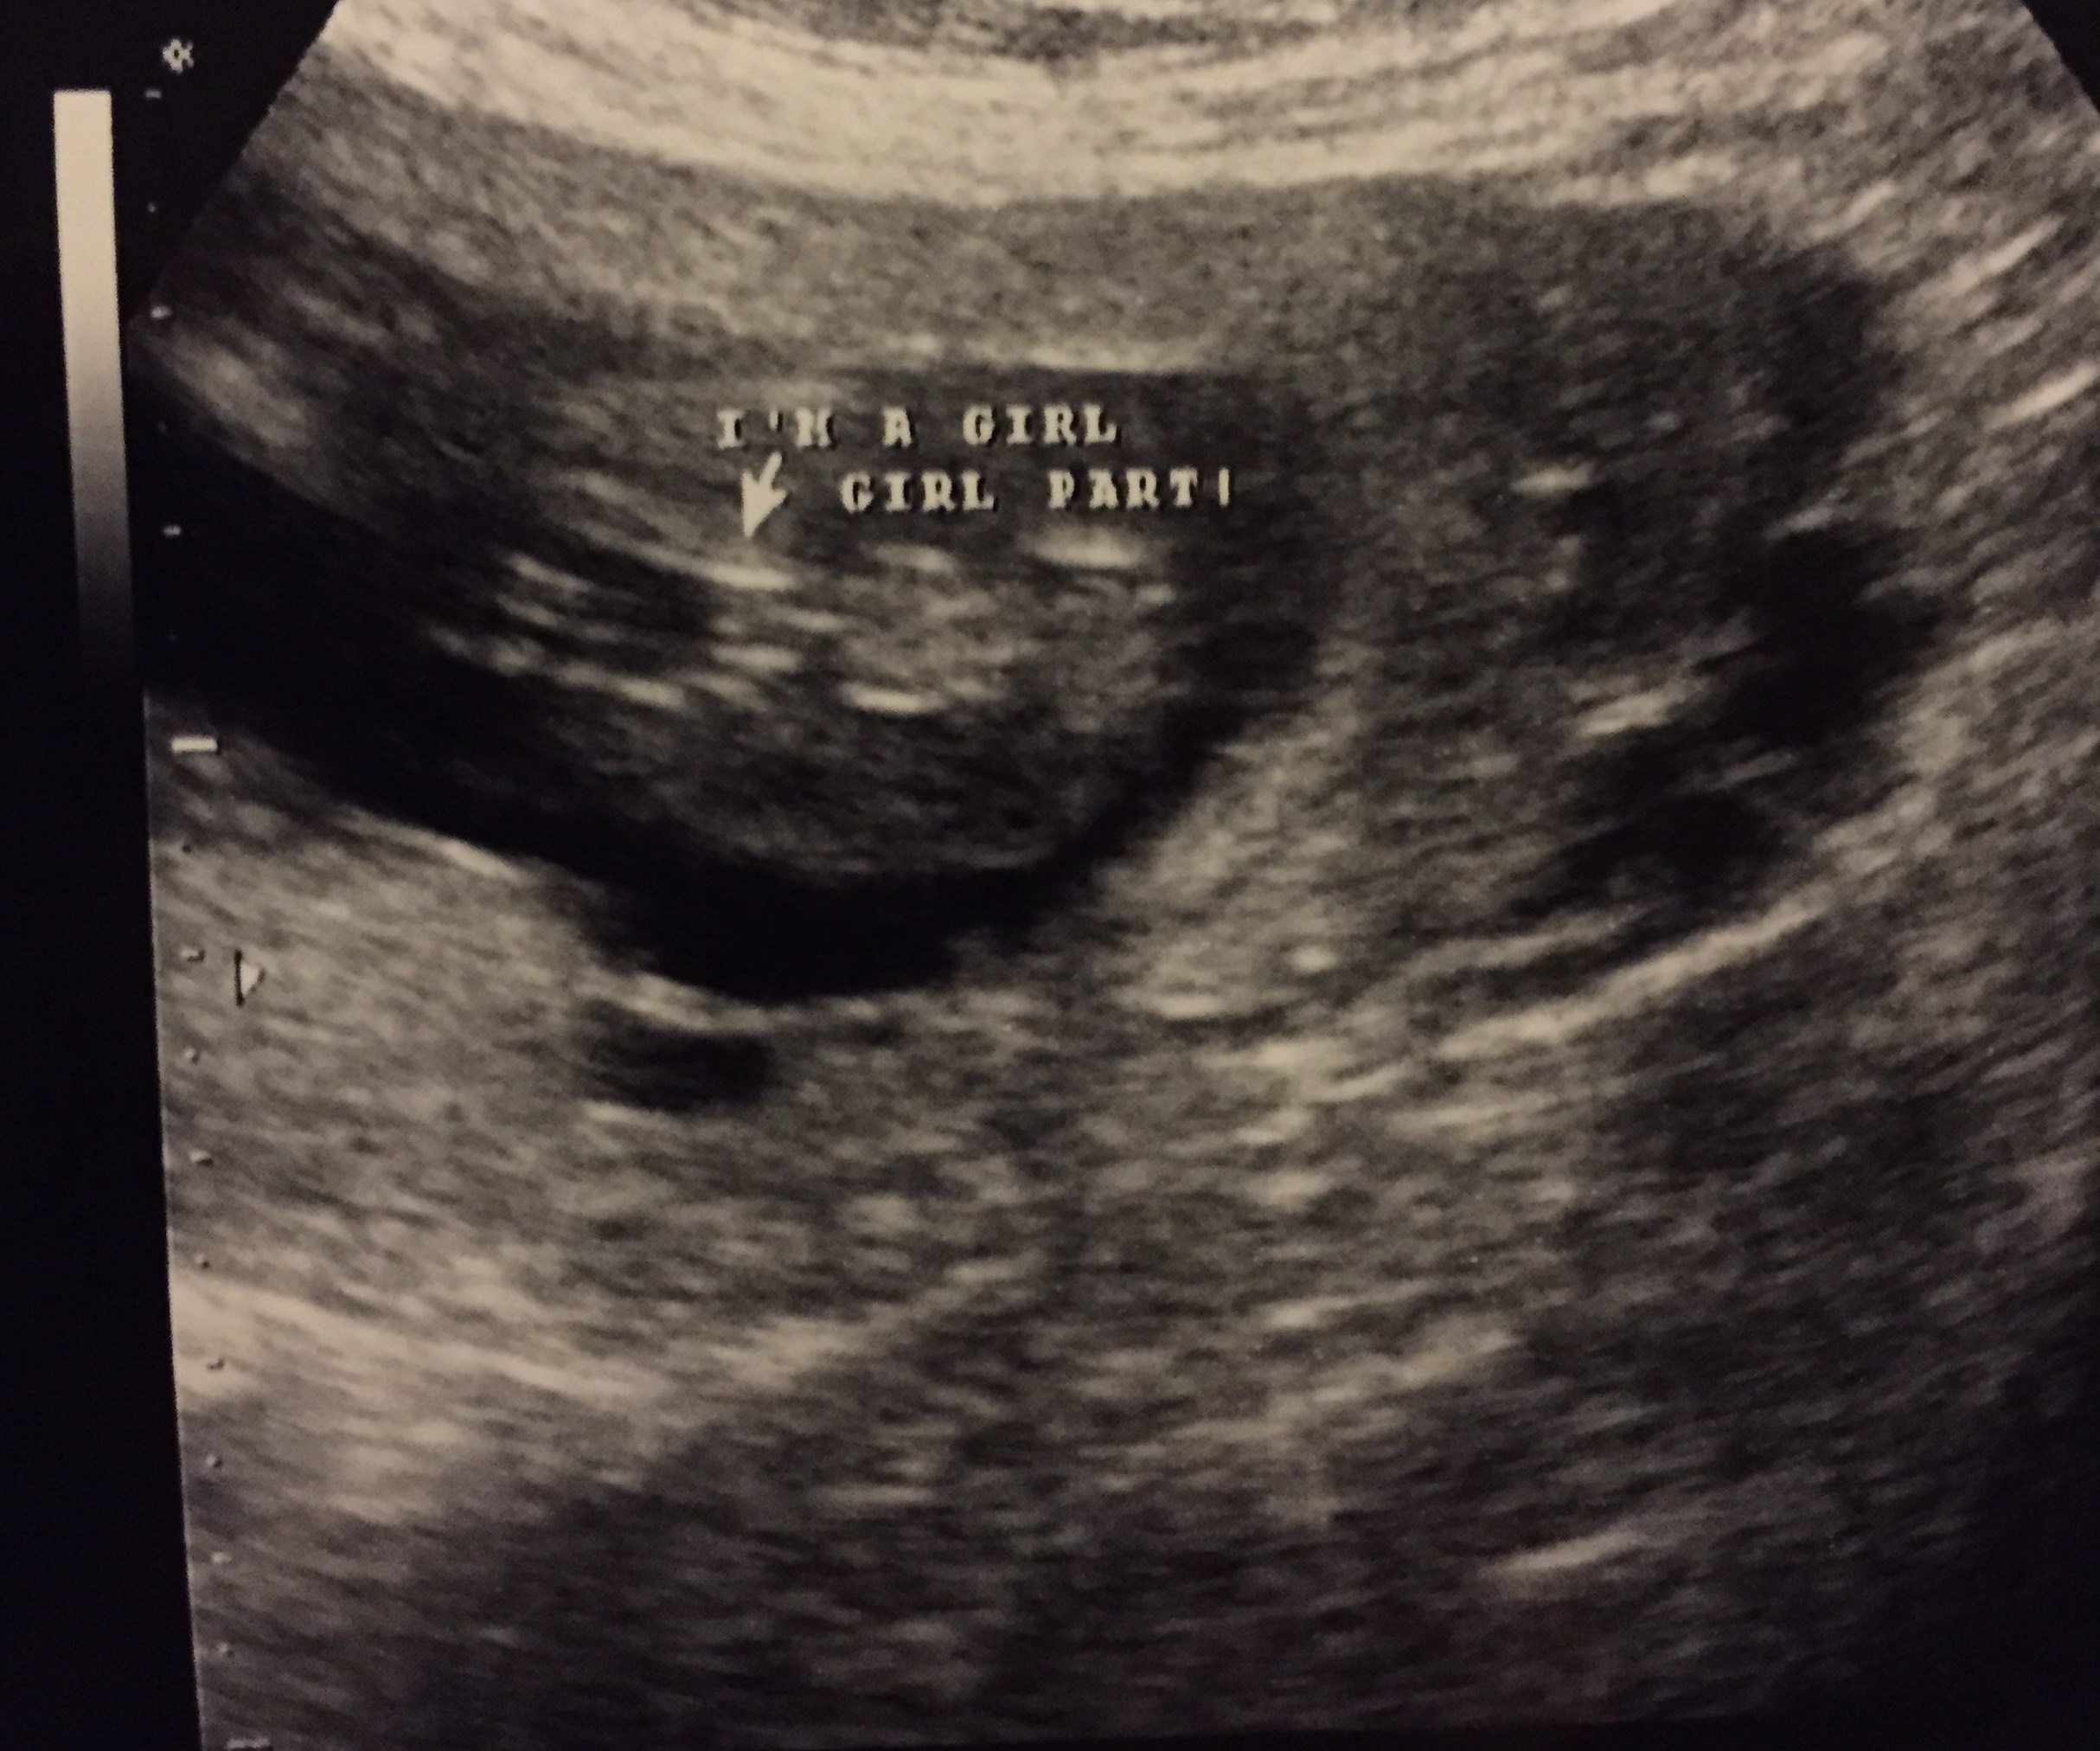

I had an elective ultrasound done and the cord was between the baby's legs the whole time. Can I get your opinions on whether this looks like cord or girly bits, please? I have boys and I'm praying this is a little princess, but I don't want to get my hopes up just yet. Attachment 29033Attachment 29034